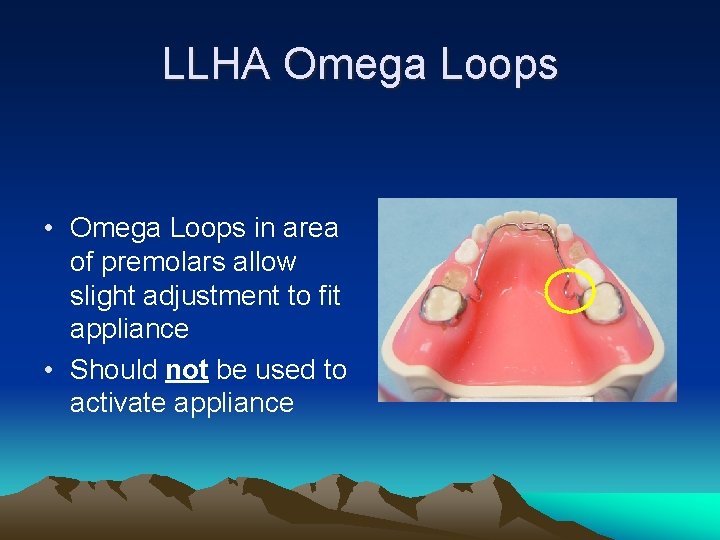

LLHA Omega Loops • Omega Loops in area of premolars allow slight adjustment to fit appliance • Should not be used to activate appliance